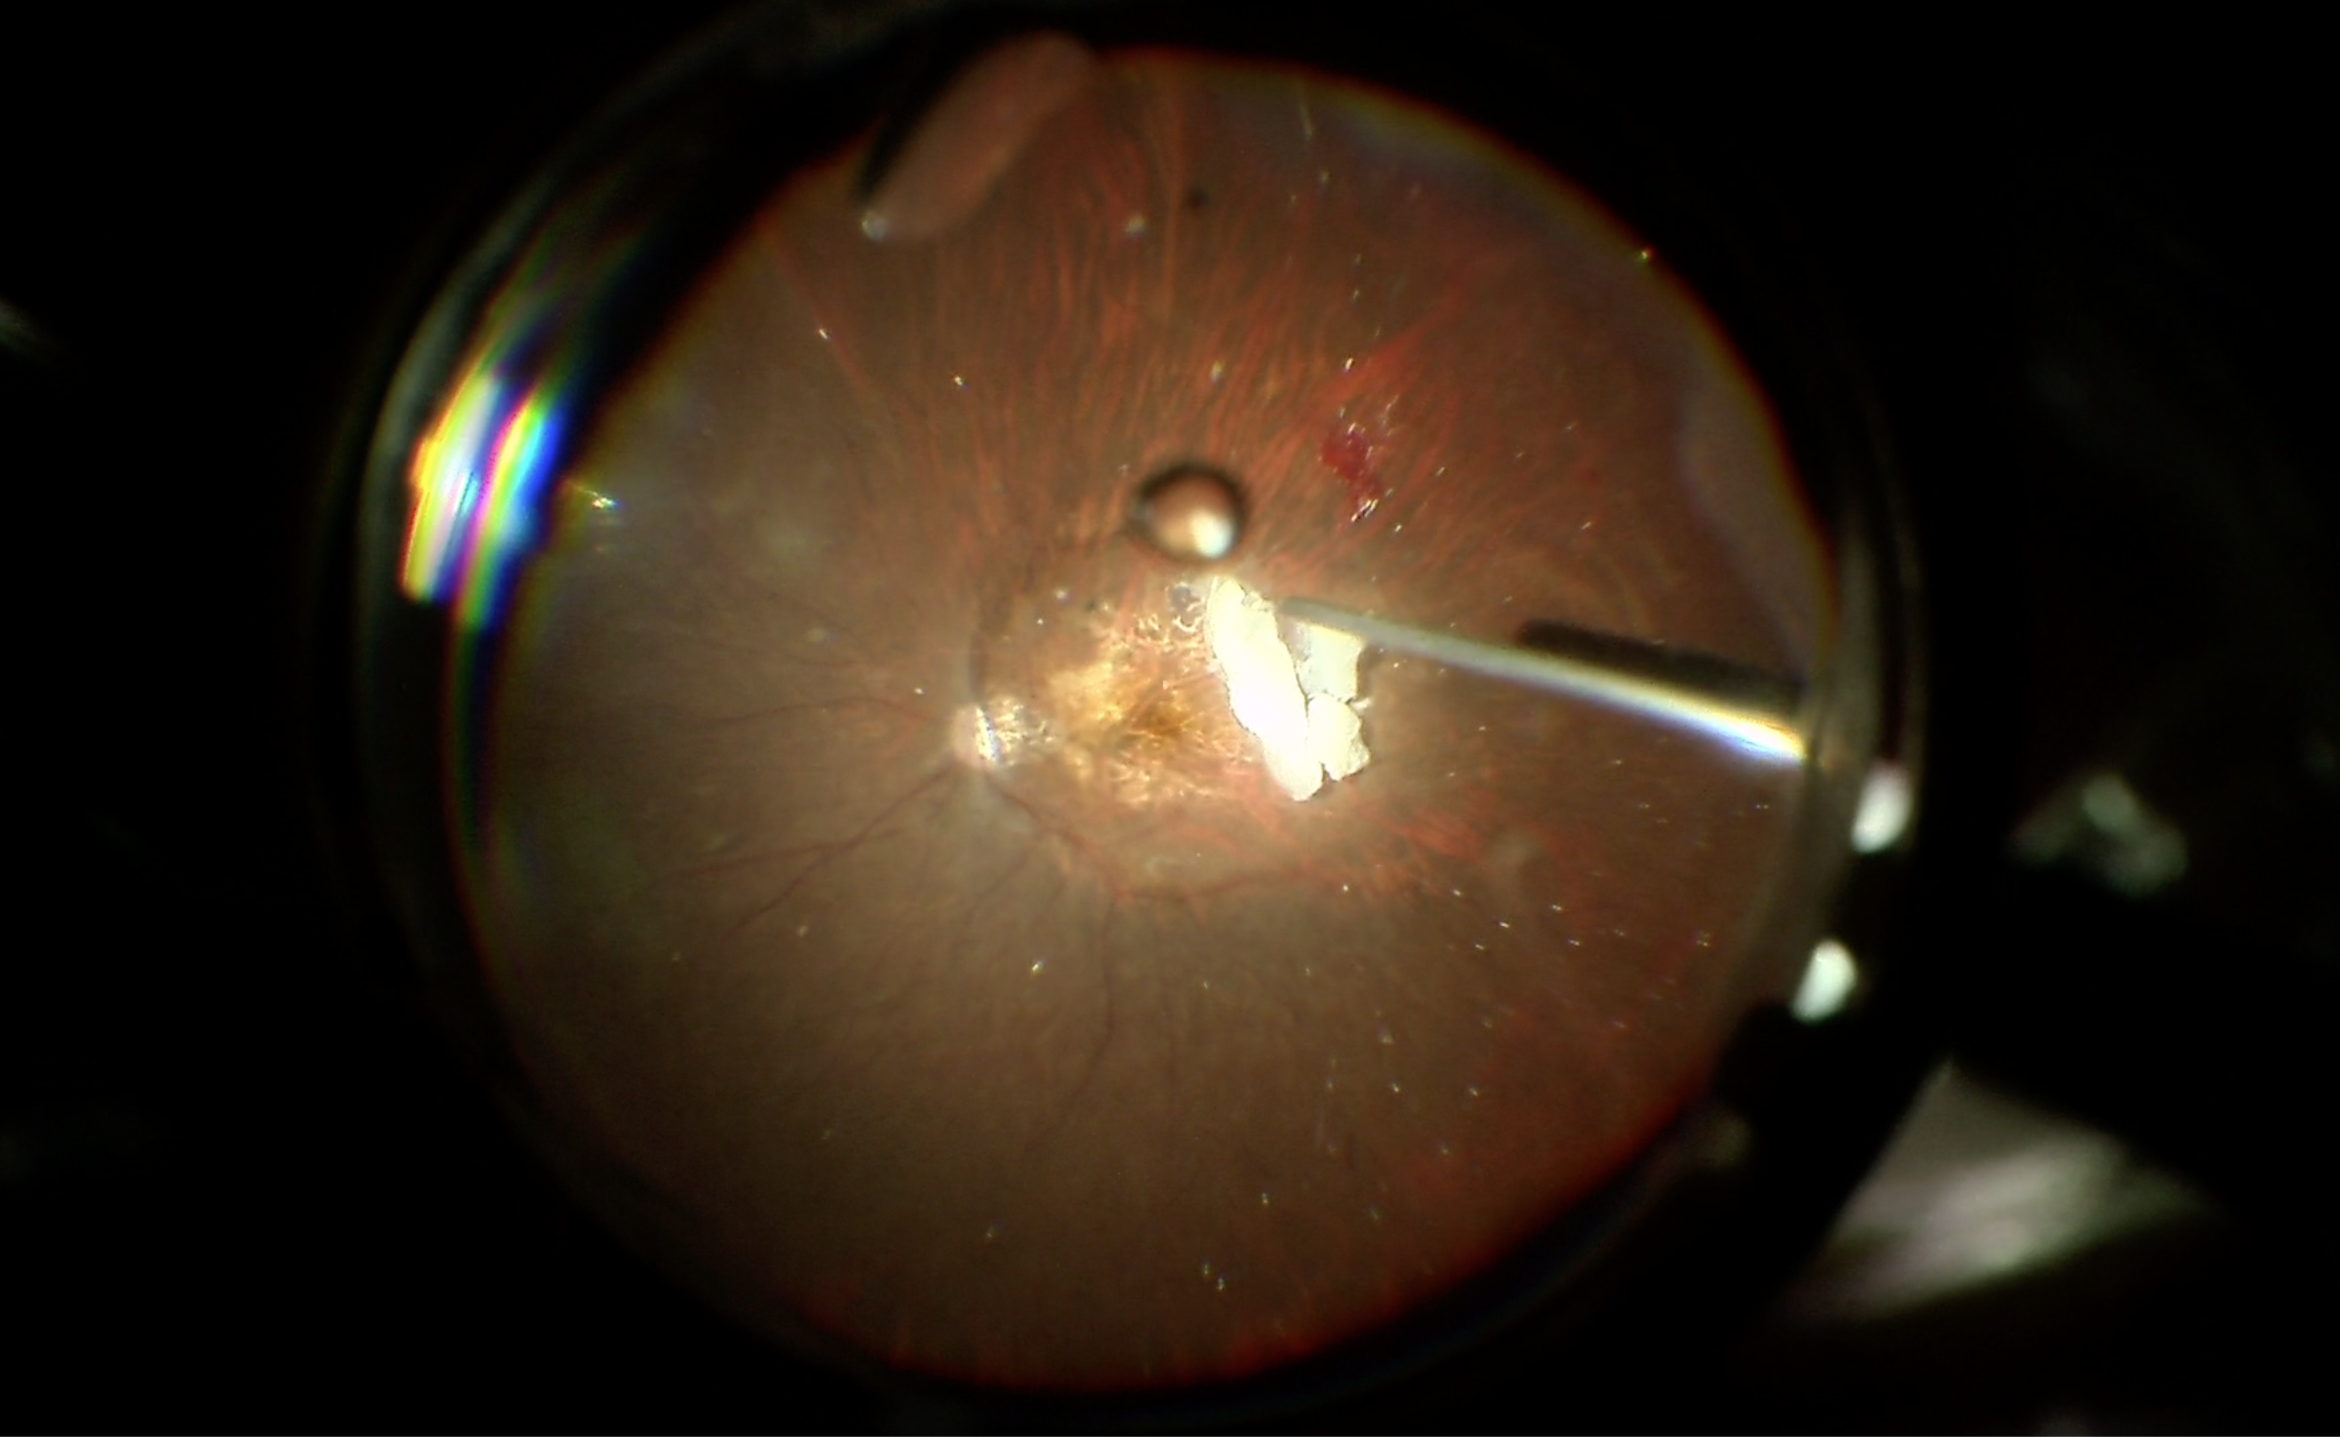

通常の白内障の手術でも細胞レベルでは白内障の細胞が多少は残り、その細胞が術後に残り、後発白内障を起こしたり、水晶体嚢の赤道部にドーナツのようなリング状の濁りを作ることがあります(ゾンマーリング)。今回の患者さんでも部分的にゾンマーリングができており、レンズを固定するのに邪魔になりそうなため、これを取ることを試みました。大部分は傷口からスルッと出てくれたのですが、一部、塊として眼底の奥に落ち込んでしまいました。こうなると少しずつ硝子体カッターで削りながら吸い取らなければならないのですが、カッターの吸引口は高速で歯が動くようになっていて、塊を弾いてしまうので、ライトの器具で塊を抑えながら少しずつ処理していきますが、塊は網膜の表面に落ちているため、拾う時には網膜を傷つけないような注意もしなければならず、地道で厄介な操作が必要になってしまいます。

硝子体の切除と眼内レンズの固定はとてもスムーズでしたが、このゾンマーリングの処理に時間がかかってしまいました。黄斑の萎縮も強いので、極端な視力改善は難しいでしょうが、レンズはきれいに入れることができたと思うので、少しでも見え方が改善してくれるといいなと思います。